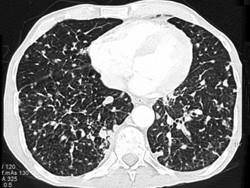

女,56岁,乳腺癌手术后,未行化疗,结合CT图像,选择最可能的诊断是 ( )A、肺结节病B、肺曲菌病C、肺结核D、间质性肺炎E、肺转移癌

问题 女,56岁,乳腺癌手术后,未行化疗,结合CT图像,选择最可能的诊断是 ( )

选项 A、肺结节病 B、肺曲菌病 C、肺结核 D、间质性肺炎 E、肺转移癌

答案 E